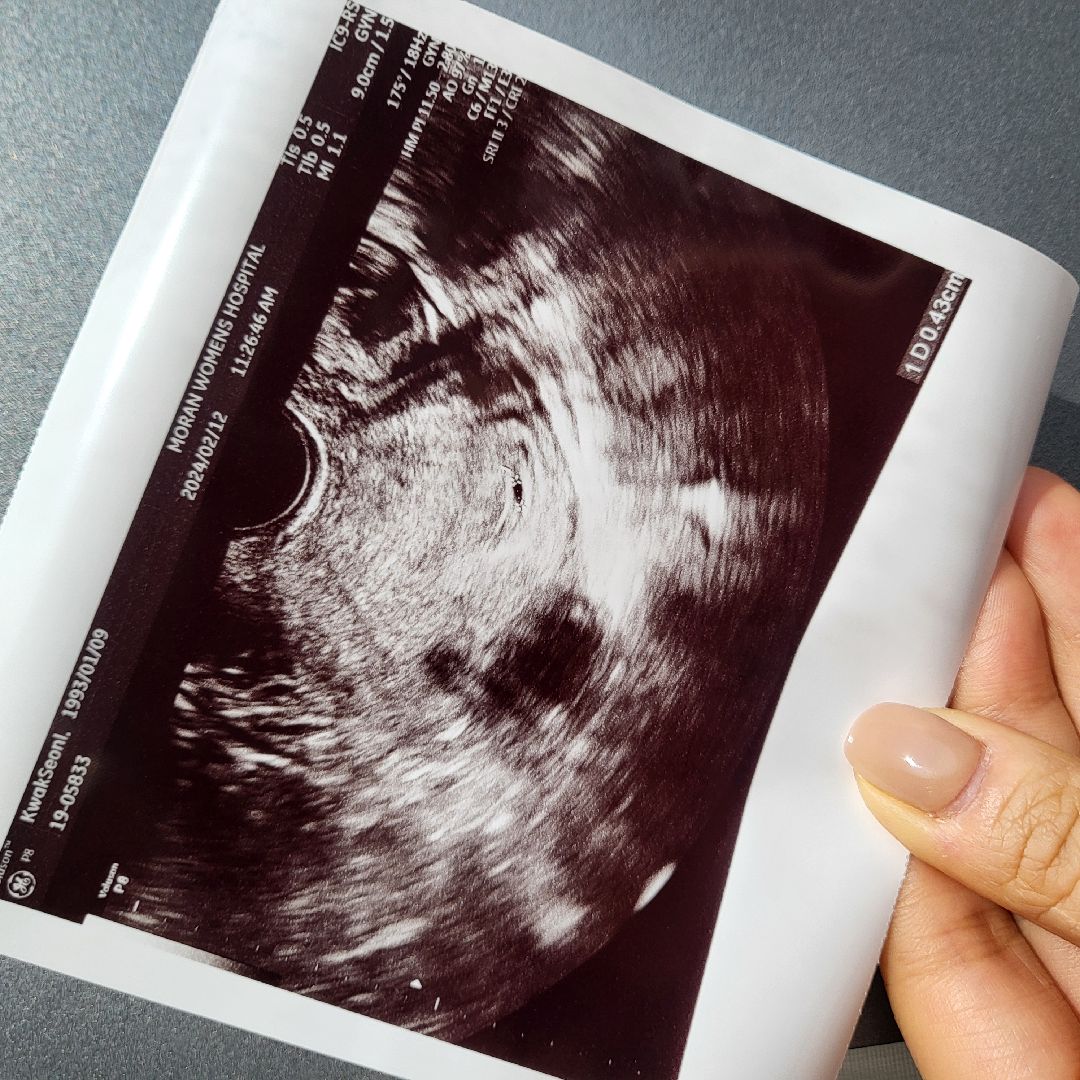

다들 아기집 말하는거맞죠?.. 저 5주3-4일 정도에 1.5cm이였는데 너무 큰거 아닌가요?……

막생기준 6주0일인데... 아기집 사이즈기준 5주 조금 안된다고 하시네요ㅠ 0.43센치....작고 소듕... 다들 첫초음파때 아기집 사이즈 어땟나요?

5주1일 1.33 이요

저는5주인줄알고 갔는데 아기집으로추정되는 크기로4주라고 일주일후에오라셧어요 0.68-0.72cm 조그매서 지금잘안보인담서

5주1일 0.89용!! 작은 난황도 봤어요 ㅎㅎ

저두 5주2일 0.5cm요!ㅋㅋㅋ